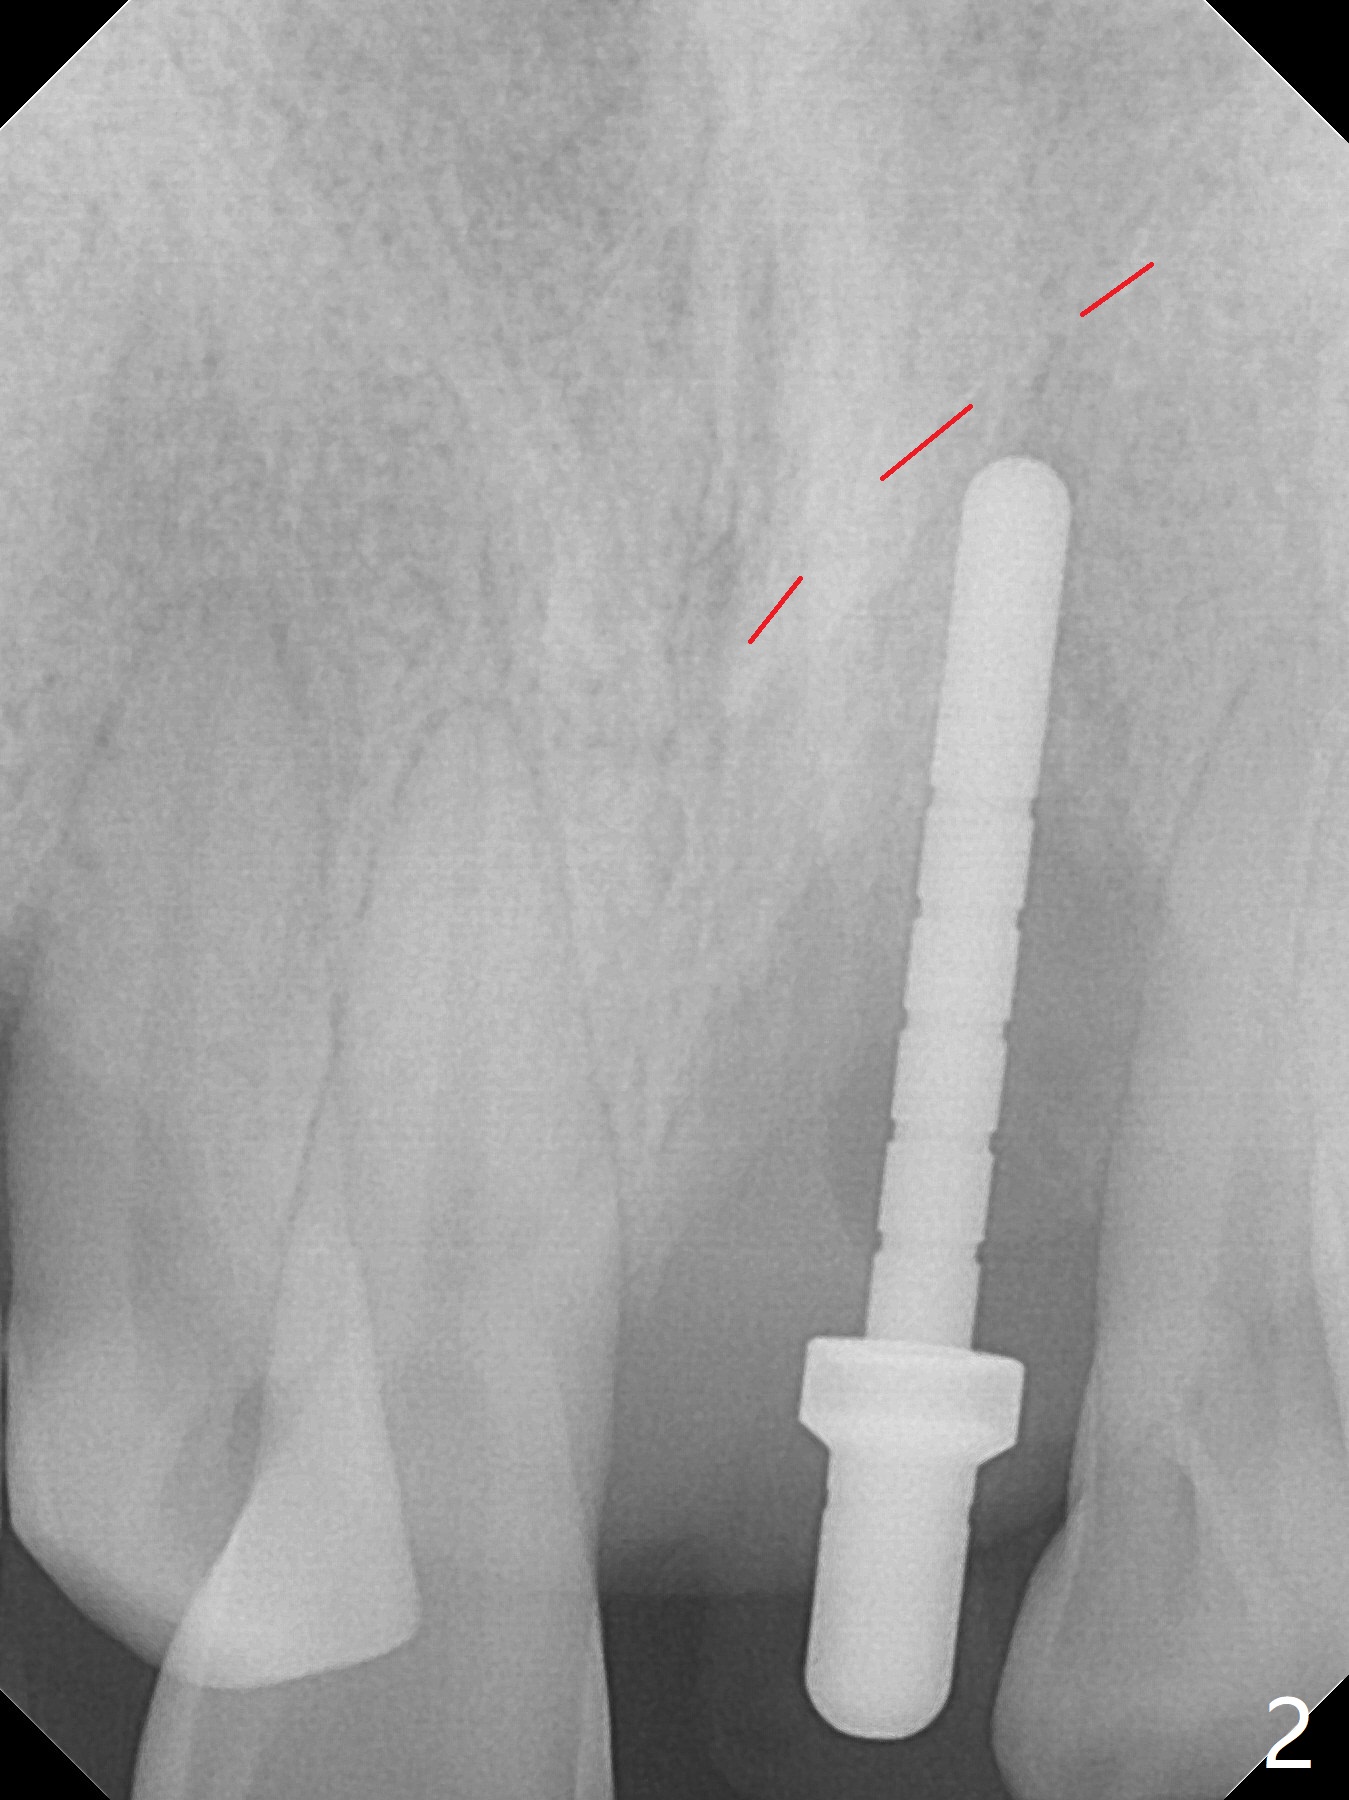

Immediately preop PA confirms loss of the buccal plate at #9 (Fig.1 *). In contrast the palatal crest is ~ 4 mm subgingival (WNL) after extraction. When initial osteotomy reaches 18 mm, there is moderate hemorrhage, probably due to close to the nasal floor (Fig.2 red dashed line). Following sequential osteotomy, a 3.8x15 mm dummy implant is placed partially (Fig.3 (pink: apical osteotomy)). After placement of an implant with the same dimension as the dummy's (Fig.4), PRF is laid against the inner surface of the buccal defect and allograft (Fig.5 *) is packed mainly in the buccal gap before and after insertion of a 4.5x5(4) mm abutment. The patient is satisfied with the immediate provisional (Fig.6: 1 week postop). The buccal margin of the provisional is shortened with exposure of bone graft to facilitate gingival downgrowth (Fig.6: 1 month postop). The buccal plate seems to collapse nearly 2 months postop (Fig.8 *), probably due to loss of the bone graft. The abutment is exposed buccally (Fig.9). The margin of the abutment is reprep and the provisional is relined so that the margin of the provisional is palatal to the buccal gingival margin. In 2-3 weeks, a temporary abutment will be used to bulk the buccal gingiva. The gingiva seems to have downgrown; the buccal plate collapse appears normal nearly 3 months postop (Fig.10). The patient is more concerned about cross bite at #7. A temporary abutment is not used. The bone graft remains in place 3.5 and 4.5 months postop (Fig.11,12 *). Between 3 and 4 months postop, the mesial surface of the abutment has been trimmed (Fig.12 >). Since the mesial surface of the tooth #10 will be reduced (white curved line) to correct the upper dental midline, an angled abutment (red line) seems to be necessary to shift the provisional distal.